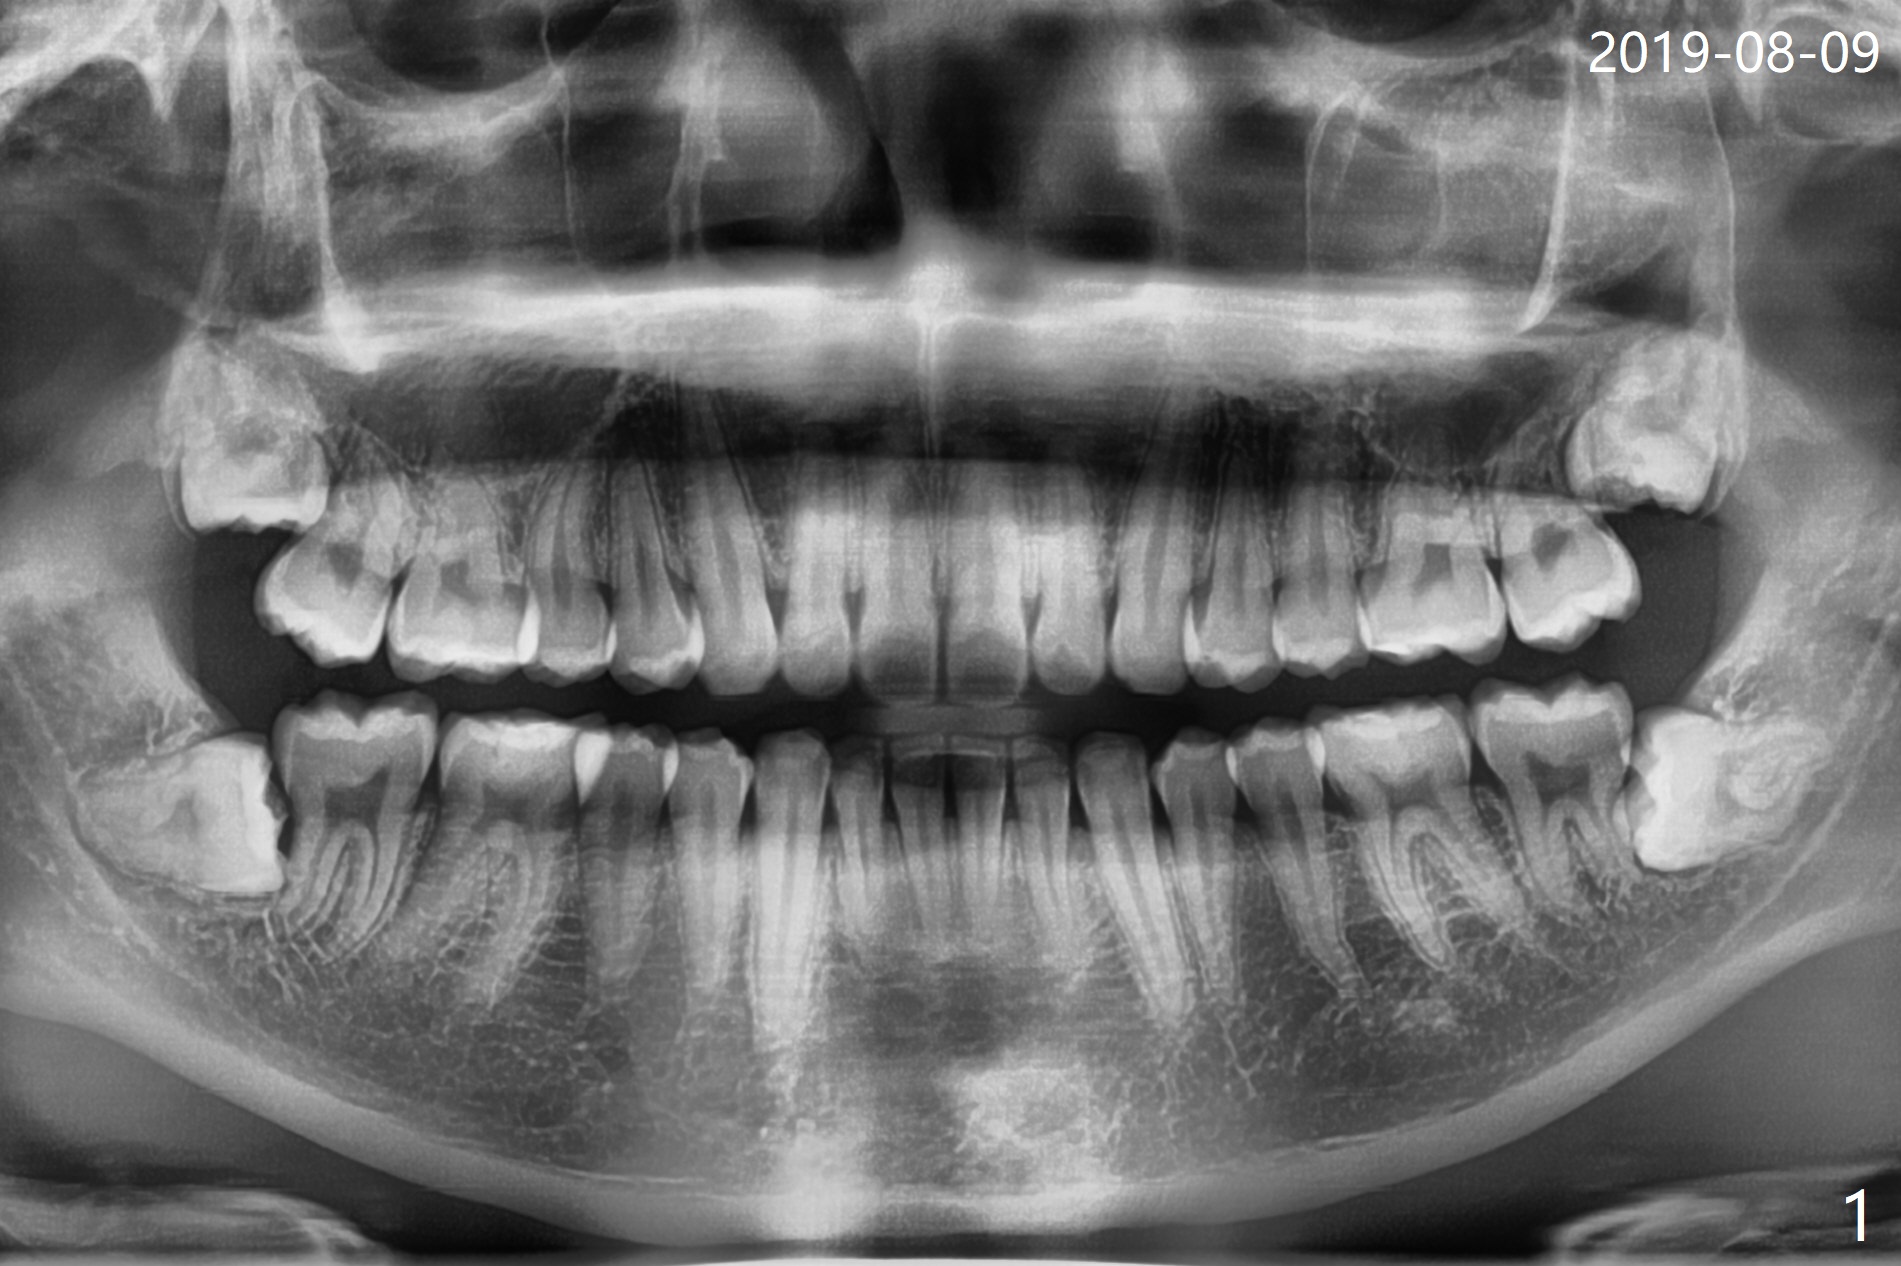

A 22-year-old man, asymptomatic, is going to have #1,16,17 and 32 extracted (Fig.1, fully bony impaction).  For the large lower sockets (actually Buccal Impaction), collagen plug (Fig.3 C) is placed in the inferior half, while Bone Cement (Bond Apatite from Augma (Fig.2,3 A)) and Osteogen plug (Fig.3 O) in the superior half at #32 and 17, respectively.  4-0 Chromic gut suture is used to close the wounds.  The four sockets heal (with increased bone density) 4 months postop (Fig.4).